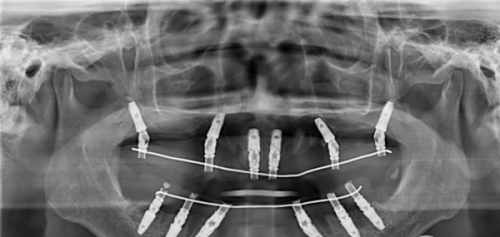

轮到我就诊时,医生非常和蔼可亲,他先仔细地询问了我的牙齿病史和目前的症状。然后让我躺在牙椅上,用专精的设备对我的口腔进行了全方面的检查。医生一边检查一边耐心地给我讲解我的牙齿情况,包括牙槽骨的密度、牙龈的健康状况等。通过详细的检查,医生发现我的牙槽骨条件还不错,这为种植牙手术提供了良好的基础。之后,医生为我安排了进一步的口腔 CT 检查,以便更正确地了解牙齿的内部结构。整个诊断过程非常细致,让我对自己的牙齿状况有了清晰的认识。

太原达美联合口腔医院的种植牙技术有特别多特色。首先,医院采用的是精良的数字化种植技术。通过口腔 CT 扫描和计算机模拟,医生可以严谨地规划种植体的位置和角度,大大提高了手术的成功几率。其次,医院的种植体品牌丰富,患者可以根据自己的需求和经济状况进行选择。再者,医院的医生团队会为每一位患者制定个性化的治疗方案,充分考虑患者的口腔状况和个人需求。末尾,医院提供完善的术后跟踪服务,医生会定期回访患者,了解修复情况并给予指导。